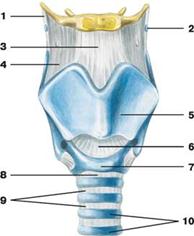

Связки и хрящи гортани (вид спереди):

Связки и хрящи гортани (вид спереди):

1 — щитоподъязычная связка; 2 — зерновидный хрящ;

3 — срединная щитоподъязычная связка; 4 — щитоподъязычная перепонка;

5 — щитовидный хрящ; 6 — перстнещитовидная связка;

7 — перстневидный хрящ; 8 — перстнетрахеальная связка;

9 — кольцевые связки трахеи; 10 — дугообразные трахейные хрящи